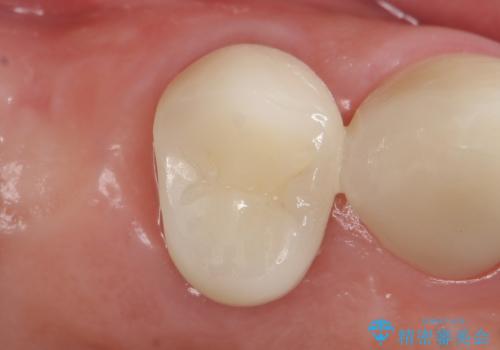

自然な仕上がりにご満足頂けました。

「うわー、自分の歯みたい!すごい!」と喜んで下さいました。

クラウンの種類:オールセラミッククラウン スタンダード